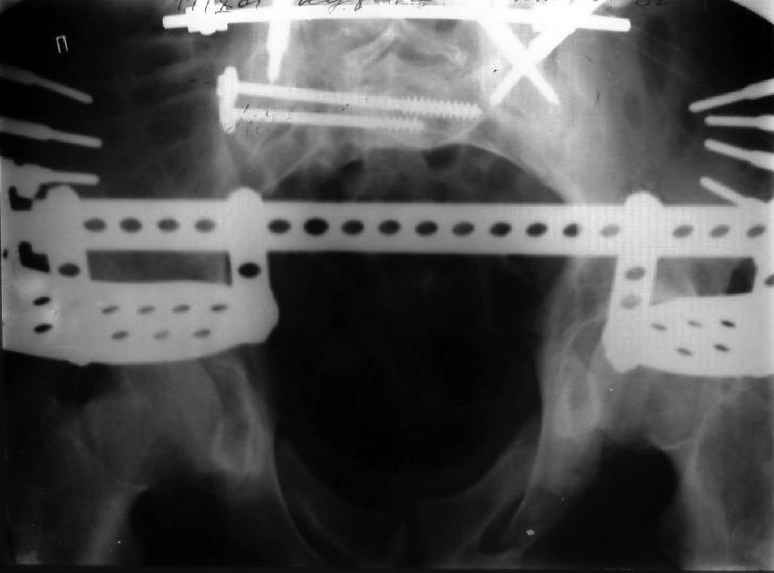

Для информации к размышлению о возможности исправления имеющейся деформации предлагаю похожий случай.